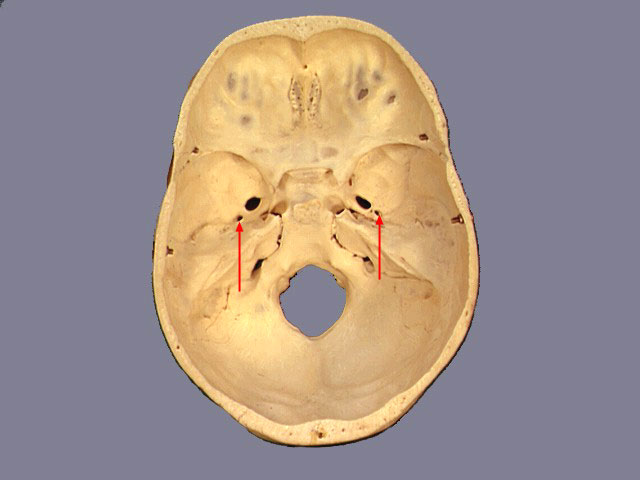

Identify the structure marked by the arrows

Jugular Foramen